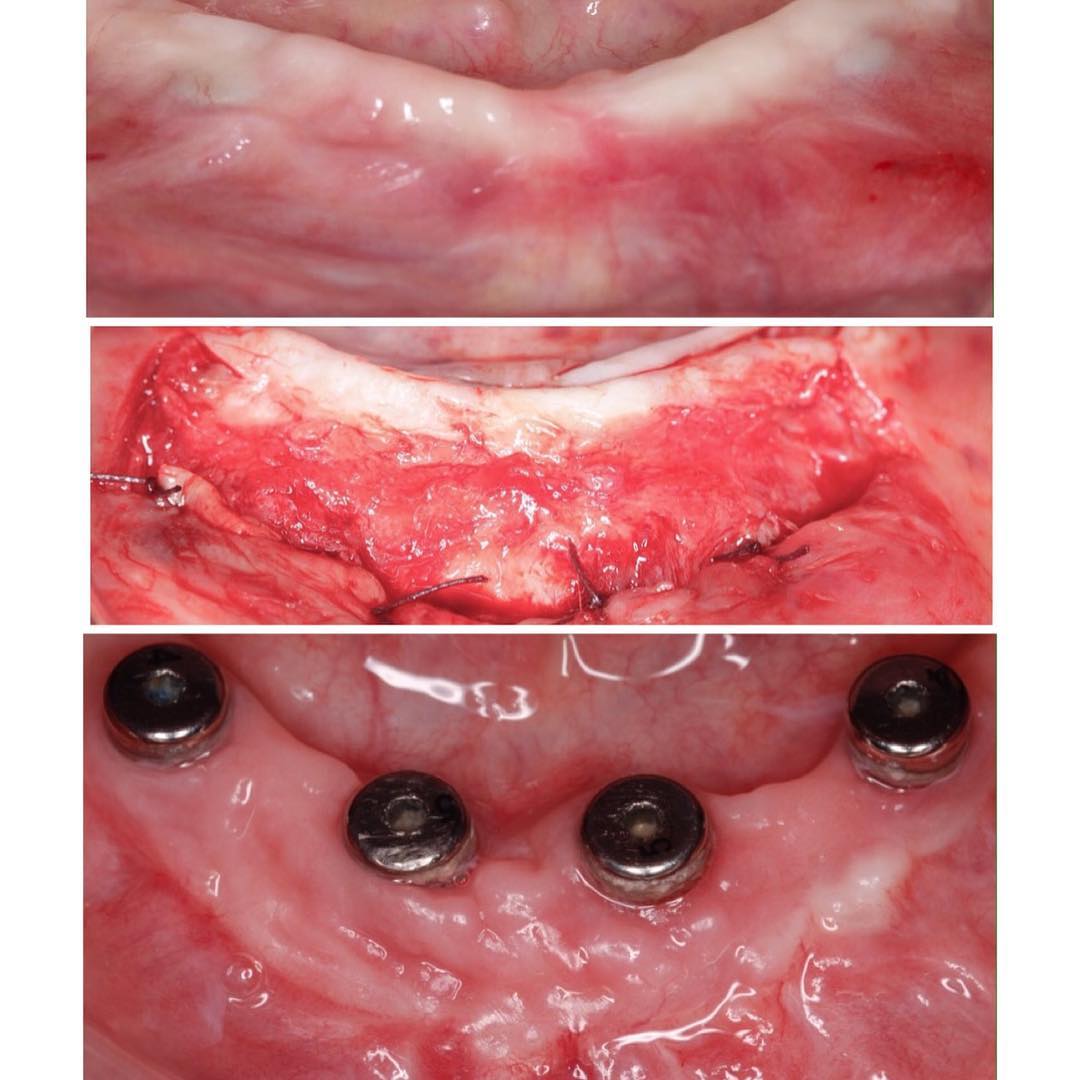

Los dientes remanentes del maxilar superior serán extraidos, se colocarán 5 implantes inmediatos flapless y 3 más con fresas de